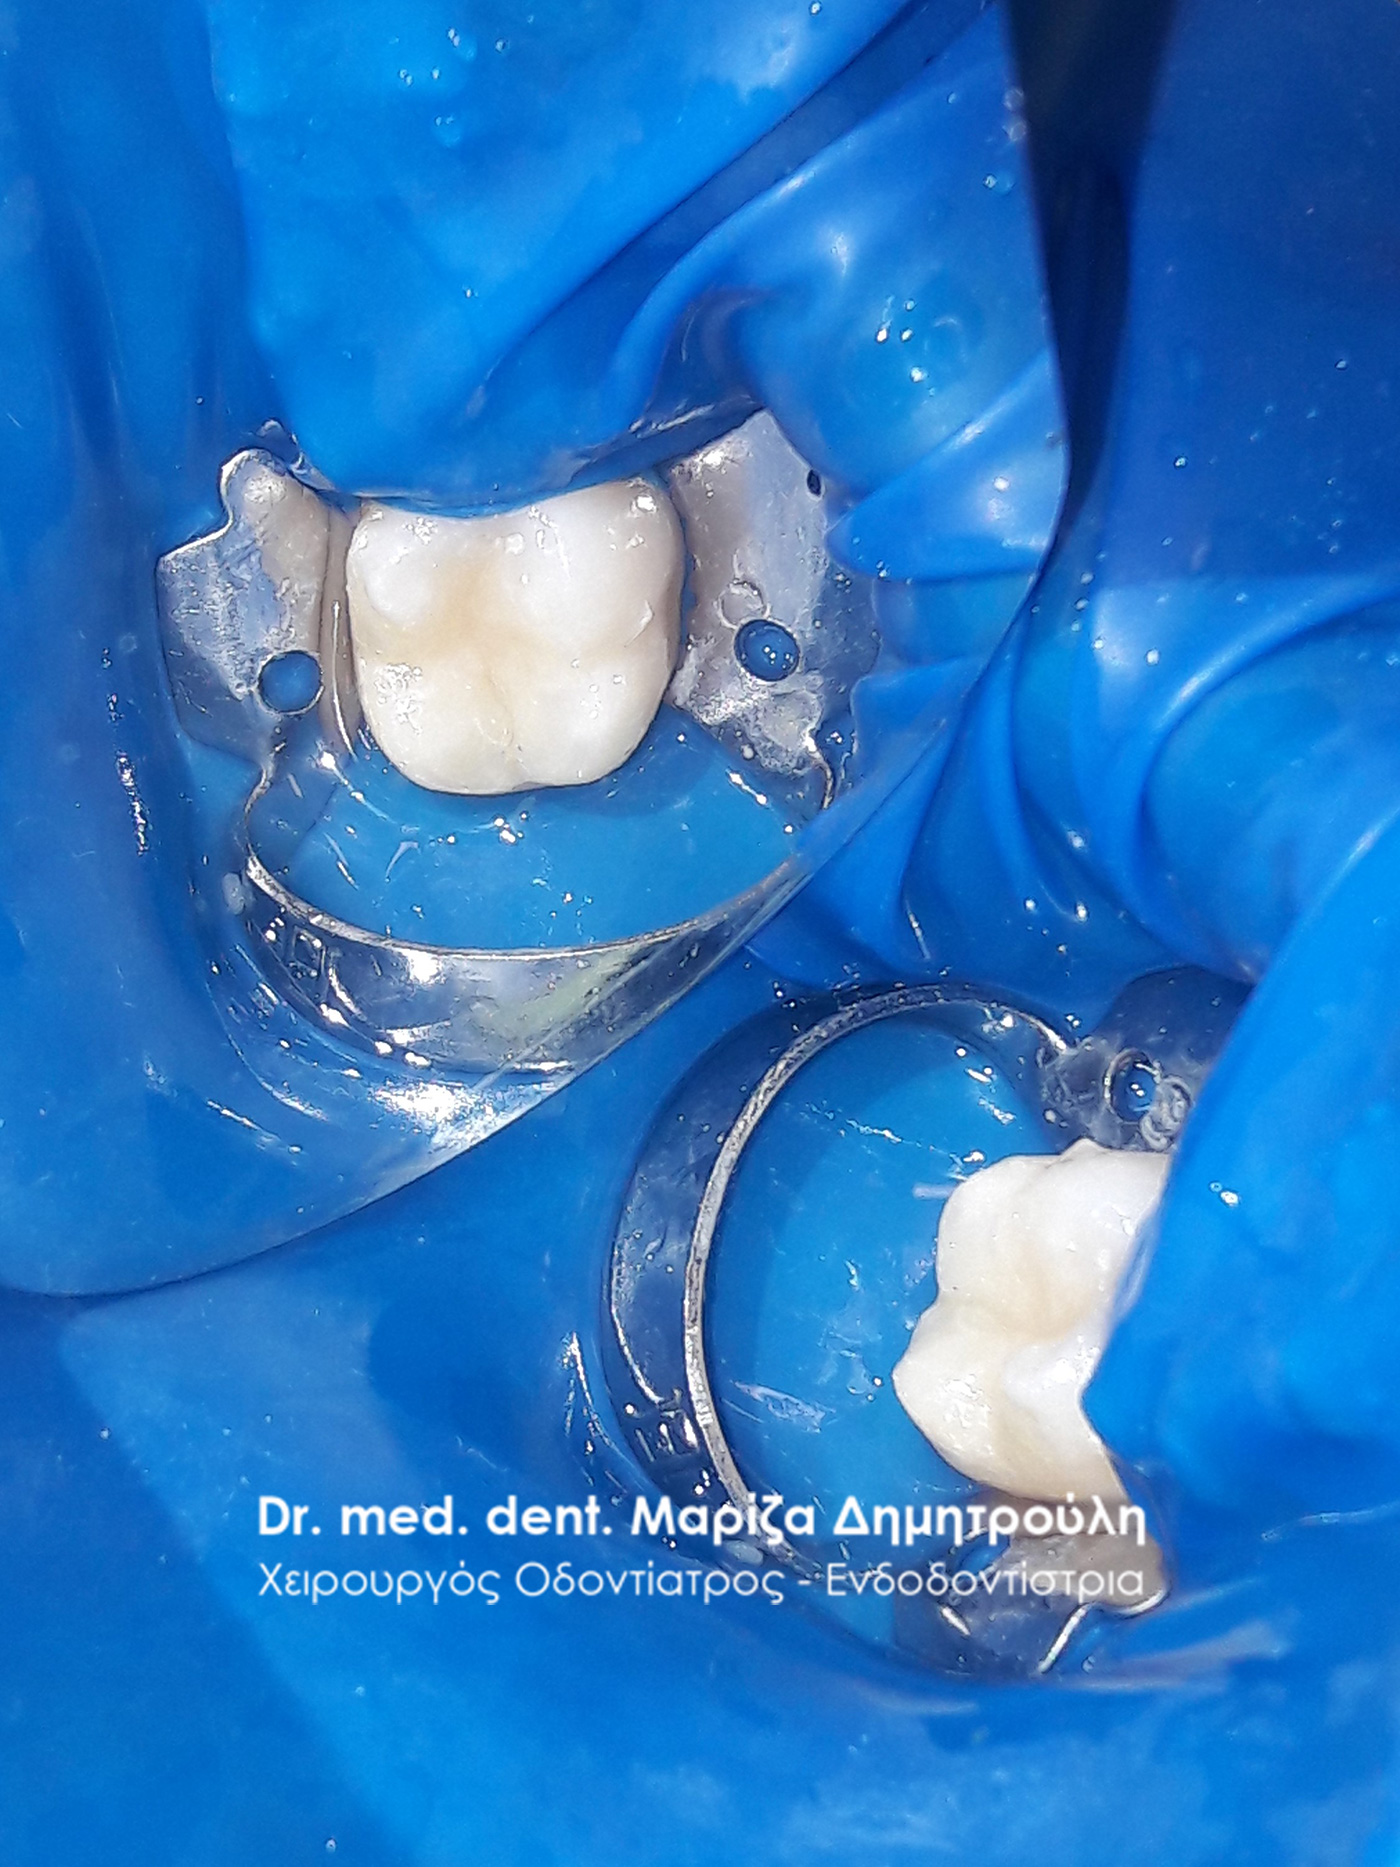

Περιστατικό – Αντικατάσταση όλων των παλιών επανατερηδονισμένων σφραγισμάτων και ολοκεραμική γέφυρα δοντιών – ζιρκονίου

Η κυρία προσήλθε στο ιατρείο με οίδημα στην αριστερή πλευρά της κάτω γνάθου. Μετά την κλινική και ακτινογραφική εξέταση των δοντιών αφαιρέθηκε η παλιά γέφυρα που είχαν τα δόντια της. Όπως δείχνουν οι φωτογραφίες αφαιρέθηκαν με πολύ προσοχή οι παλιοί μεταλλικοί άξονες από το εσωτερικό των ριζών χωρίς να προκληθεί καμία βλάβη στα υπολείμματα των ριζών των δοντιών. Οι εναπομείναντες ρίζες δοντιών χρησιμοποιήθηκαν ως “φυσικά εμφυτεύματα” και πιο συγκεκριμένα πάνω στις ρίζες των δοντιών χτίστηκε ολόκληρο κολόβωμα δοντιού χρησιμοποιώντας ειδικούς άξονες υαλονημάτων. Στο γομφίο αφού αφαιρέθηκε η παλιά θήκη και απομακρύνθηκε ο μεταλλικός άξονας με τον ίδιο προσεχτικό τρόπο διαπιστώθηκε οτι η μία ρίζα του δοντιού ήταν πολύ κατεστραμμένη οπότε και αφαιρέθηκε. Η άλλη μισή ρίζα ανασυστάθηκε με άξονα υαλονημάτων και παρασκευάστηκε αναλόγως ώστε να δεχθεί τη μελλοντική γέφυρα ζιρκονίου. Ο πρώτος προγόμφιος επίσης προετοιμάστηκε αναλόγως (απονεύρωση και ανασύσταση δοντιού) ώστε να χρησιμοποιηθεί ως στήριγμα γέφυρας. όταν ολοκληρώθηκαν όλες οι απαραίτητες προεργασίες λήφθηκε αποτύπωμα το οποίο εστάλει στον οδοντοτεχνίτη για την κατασκευή ολοκεραμικής γέφυρας ζιρκονίου. όταν η γέφυρα ήταν έτοιμη συγκολλήθηκε στο στόμα της ασθενούς.

Απονεύρωση του πρώτου προγόμφιου με τη χρήση ελαστικού απομονωτήρα